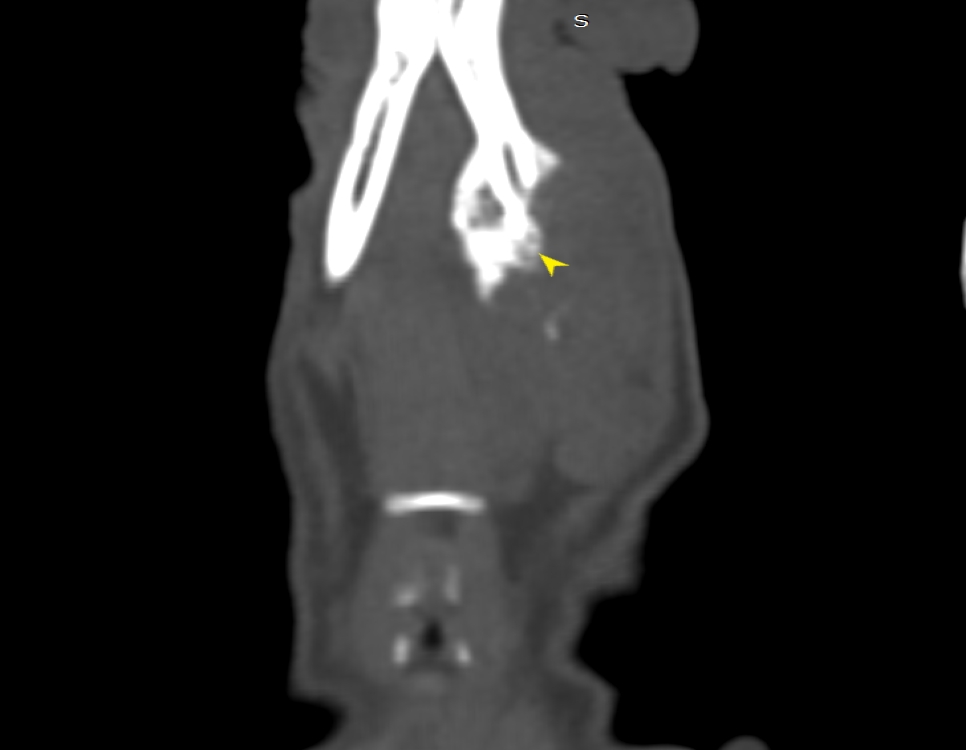

狗狗後腳癱瘓也有可能是血栓 不一定是骨骼神經肌肉問題喔

後肢癱瘓的柴柴經由他院轉診來築心做電腦斷層掃瞄因為狗狗以前病史有椎間盤突出問題

所以以為是脊椎問題想要來評估手術

掃瞄結果診斷為動脈血栓造成

主動脈血栓栓塞是一種急性且危及生命的疾病,當血液凝塊從心臟或其他部位脫落,經過血液循環流向並卡住動脈中的某些血管,造成局部的血液供應中斷、相應部位的器官或組織缺氧,將引起疼痛、損傷甚至壞死。

此患犬在電腦斷層影像以及後續追蹤的超音波下都可見明顯血栓影像